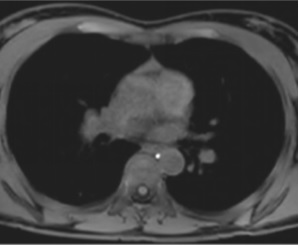

MR Lymphangiogram:特发性乳糜胸 Idiopathic Chylothorax

显示左侧静脉角的单个胸导管。在左侧的胸中三分之一中显示主动脉前渗漏。